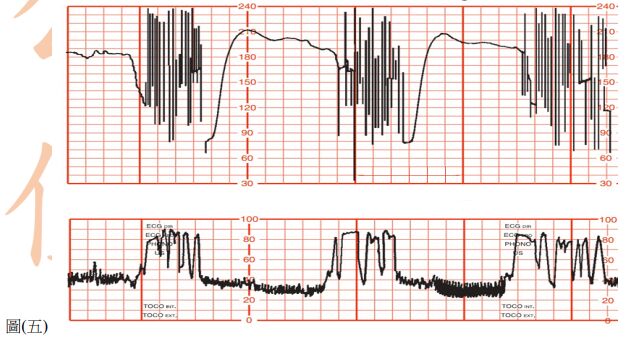

61. 懷孕 39 週第一胎孕婦,因早期破水而入院待產,剛入院時子宮頸未開,宮縮不規則,醫囑給予 oxytocin,待產三小時後,fetal monitor 顯示有tachycardia 及 loss of variability,如圖(五),下列初步處置,何者最不適當? (A) 讓產婦採左側躺 (B) 陰道內診 (C) 給予待產婦氧氣吸入 (D) oxytocin點滴加量